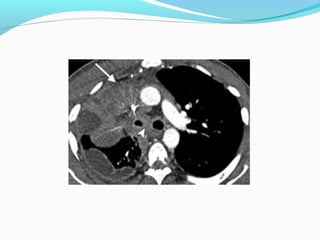

PANCOAST TUMOR

OPERABLE OR NOT?